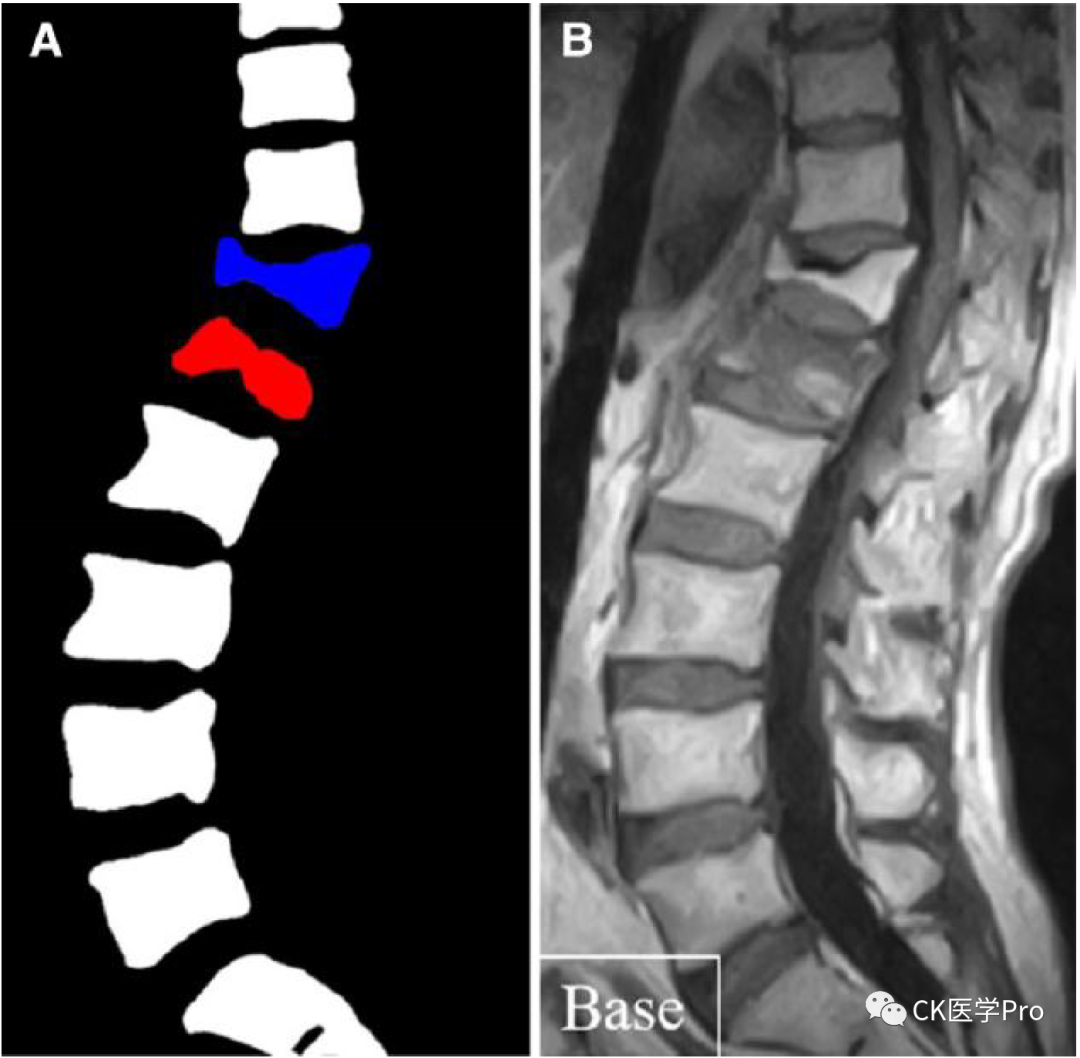

由于创伤后立即拍摄的常规脊柱X光片有时不会显示形态变化,因此还使用了磁共振断层扫描(MRT)和CT等先进的医学成像方法。例如,MRT常被用于检测骨髓水肿,作为椎体骨折的近期指标。临床上,如果考虑椎体强化,则此类信息可作为决策支持(AJNR Am J Neuroradiol. 2018;39(5):798-806)。在这方面,最近开发了一种基于AI的算法,用于自动检测新鲜的骨质疏松性椎骨骨折,其中“新鲜”被定义为在相应损伤后的3个月期间(Spine J. 2021;21(10):1652-1658)。最终选择的人工智能算法是4种不同CNN模型的组合(即“集成”),其性能最佳,与2名经验丰富的脊柱外科医生的性能相当。该人工智能工具的图像输出提供了椎骨的颜色编码分类,分为“正常”、“新鲜骨折”和“陈旧性骨折”(图2)。作者得出结论,本研究中开发的算法可能有助于减少新鲜骨质疏松性椎体骨折的误诊,从而有助于骨质疏松症患者的日常护理,尤其是在没有放射科医生或脊柱外科医生的医院中。然而,独立于一些方法上的限制,例如相对较小的训练数据集,1个主要的限制是该算法没有被训练来识别病理性骨折,例如与转移性骨疾病相关的病理性骨折。图2 (A)自动骨折检测并分类为“正常”(白色)、“新鲜骨折”(红色)和“陈旧性骨折(蓝色)”后的图像输出。(B)基线;原始图像。http://creativecommons.org/licenses/by/4.0。